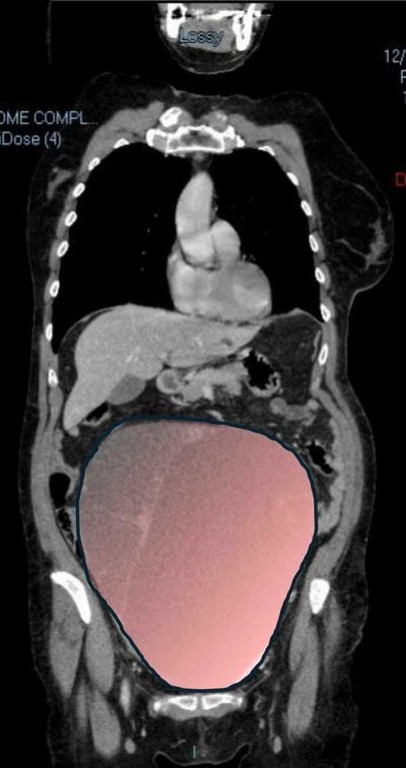

Il caso, definito dai medici un evento “normalmente eccezionale”, è stato preso in carico dalla Chirurgia Ginecologica mininvasiva dell’ospedale Sant’Anna di Torino, diretta dal dottor Paolo Petruzzelli. Nonostante le festività imminenti, la macchina della sanità piemontese si è attivata con una rapidità straordinaria: il 23 dicembre la paziente è stata sottoposta a un intervento durato sei ore che ha visto l’asportazione di una massa di ben 6 chilogrammi e un diametro di 28 centimetri.